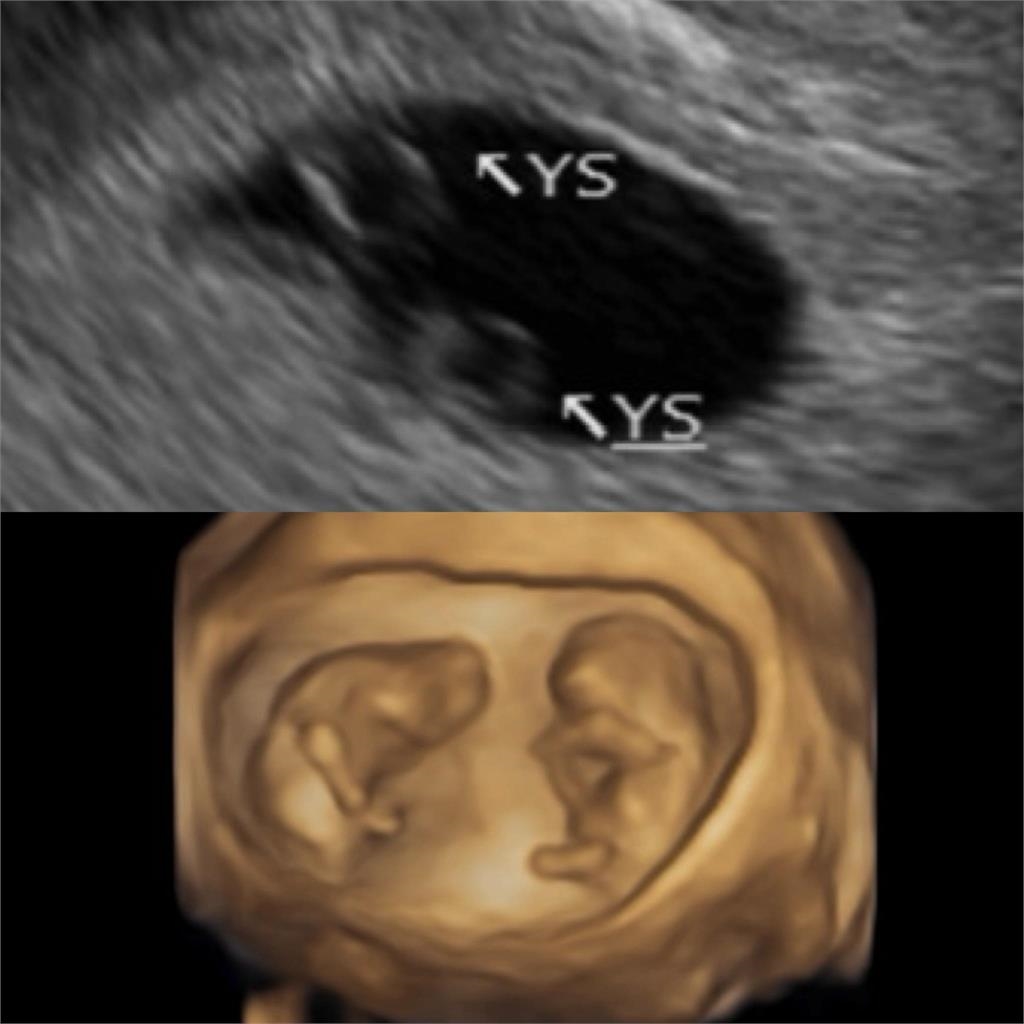

鄭家純在臉書指出:「向大家報告喜事,阿純目前懷孕12週,是同卵雙胞胎。上次有好好跟無緣的小孩介紹阿寶,像媒人一樣把人格特質、身家調查都說得很詳細,推薦寶寶回來,沒想到還多揪了手足一起來。」她進一步回憶,2月初沒等到月經來,一直等一直等,等到胸部的觸感變得跟上次懷孕很像,接著在過年除夕那天,驗孕棒出現淡淡的第二條線,也就是說小產後月經還沒來就又懷孕了。鄭家純透露,知道是雙胞胎是在5週,驚喜只有一下下,因為同卵雙胞胎比異卵的風險高,還有分單羊膜或雙羊膜。寶寶們很貼心,讓她在6週就聽到心跳,聽到的瞬間眼淚就掉下來,因為上次沒有聽到。產檢後,她才有勇氣再度開始寫懷孕日記。8週時確認是雙羊膜,安心很多,不用再查資料查到失眠。